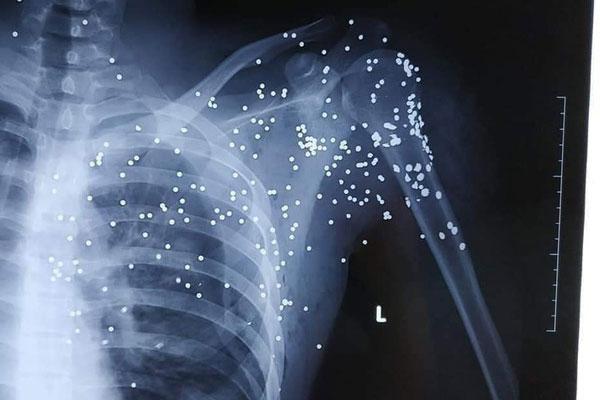

Ảnh chụp X - Quang được cho là của nạn nhân bị thương do trúng đạn sau vụ nổ súng. (Ảnh Facebook).

Theo thông tin ban đầu, vụ nổ súng xảy ra vào tối 23/11, tại địa bàn huyện Kiến Xương. Nguyên nhân được cho là do xảy ra mâu thuẫn, tranh chấp giữa hai nhà xe. Vụ việc khiến ít nhất một người bị thương nặng được đưa đi cấp cứu ngay sau đó.